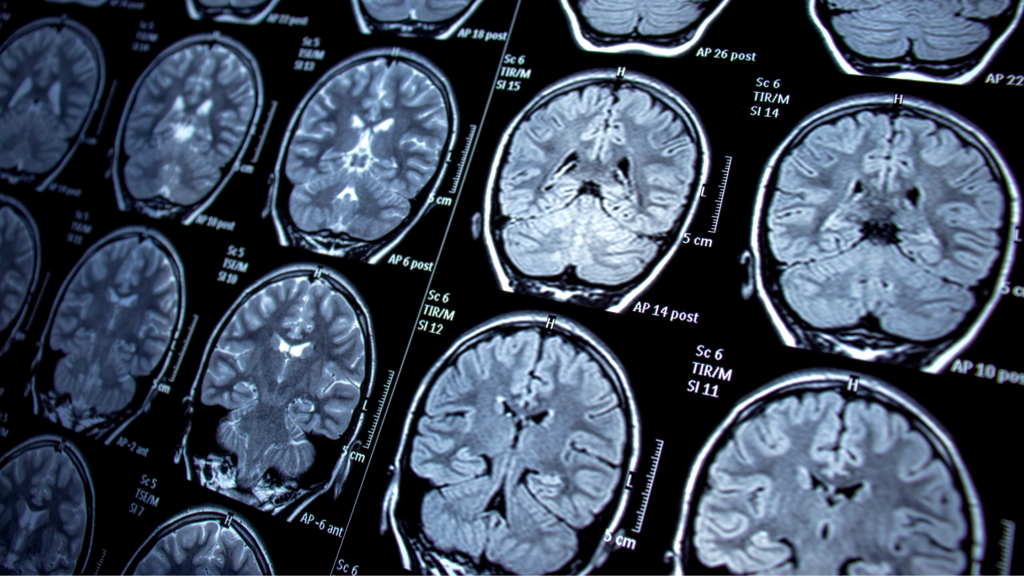

Seizures are sudden bursts of electrical brain activity. They arise when brain cells communicate in an unusual, overly coordinated pattern, often causing loss of consciousness and muscle control. Around 50 million people across the globe are affected by epilepsy1. Out of these 50 million, it is estimated that approximately one third experience seizures which cannot be controlled by medication (drug-resistant or intractable epilepsy) .